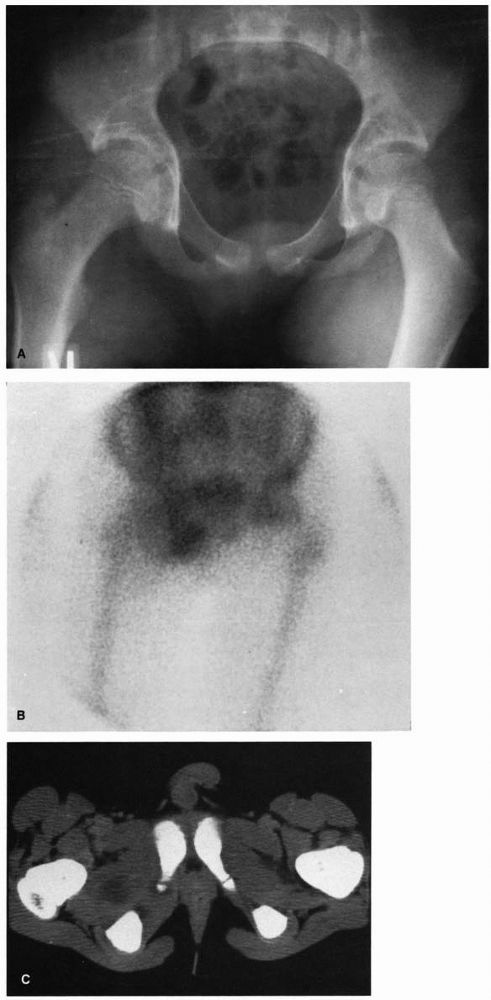

FIGURE 5-4. Eight-year-old boy with osteomyelitis of the pubis and a pelvic abscess. (A) AP radiograph of the pelvis of this child demonstrating no bony abnormalities. (B) Technetium-99m bone scan demonstrating increased uptake of the isotope in the region of the right pubis. (C) CT scan through the obturator region of the pelvis demonstrating an abscess in the obturator region of the right hemipelvis.

hematogenous osteomyelitis of the pelvis. If this occurs, surgical

drainage of the abscess is necessary. A child with acute hematogenous

osteomyelitis of the pelvis should be evaluated in the same manner as

the child with an infection of a long bone, with an appropriate history

and physical examination. In addition, laboratory data should be

obtained. Bone aspiration should also be performed, and antibiotics

should be started once all cultures have been obtained. Because of the

possibility of developing an intrapelvic abscess that is not detectable

either on physical examination or through needle aspiration, CT or MRI

scanning of the pelvis should be performed. If an abscess is seen, it

should be drained through an appropriate surgical approach and the

child treated with antibiotics to sterilize the bone (Figure 5-4).